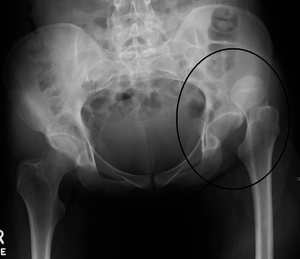

- Hip AP and lateral views

- Posterior Dislocation: AP view femoral head posterior and superior to acetabulum

- Anterior Dislocation: AP view shows femoral head in obturator foramen (inferior to acetabulum)